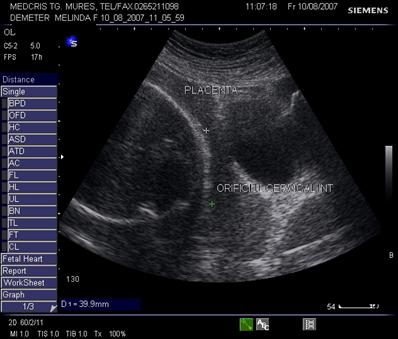

Fig. nr.217. Placenta praevia centrala la 15 saptamani ( linia indica raportul placenta praevia cu orificiul cervical intern)

Fig. nr.218. Placenta praevia complet centrala , la aceeasi sarcina ca in figura precedenta, dar la 28 saptamani gestationale